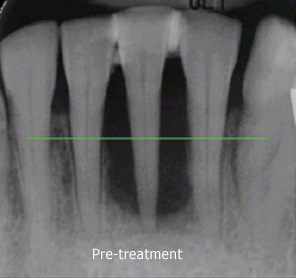

Gingivitis can progress to periodontitis, and once this occurs generally surgical intervention is usually necessary to eliminate the deep pockets which develop between the teeth and gums. If these pockets persist, they become "privileged sites" for bacteria to organize even more colonies.

Traditional gum surgery involves cutting away some of the gum tissue, and reshaping the bone underneath. LANAP is a progressive technique using a specialized laser to destroy the bacteria that cause the disease, and alter the tissue so that it has the opportunity to heal. The use of the laser is less invasive than traditional scalpel surgery, and results in a much faster and less painful recovery.